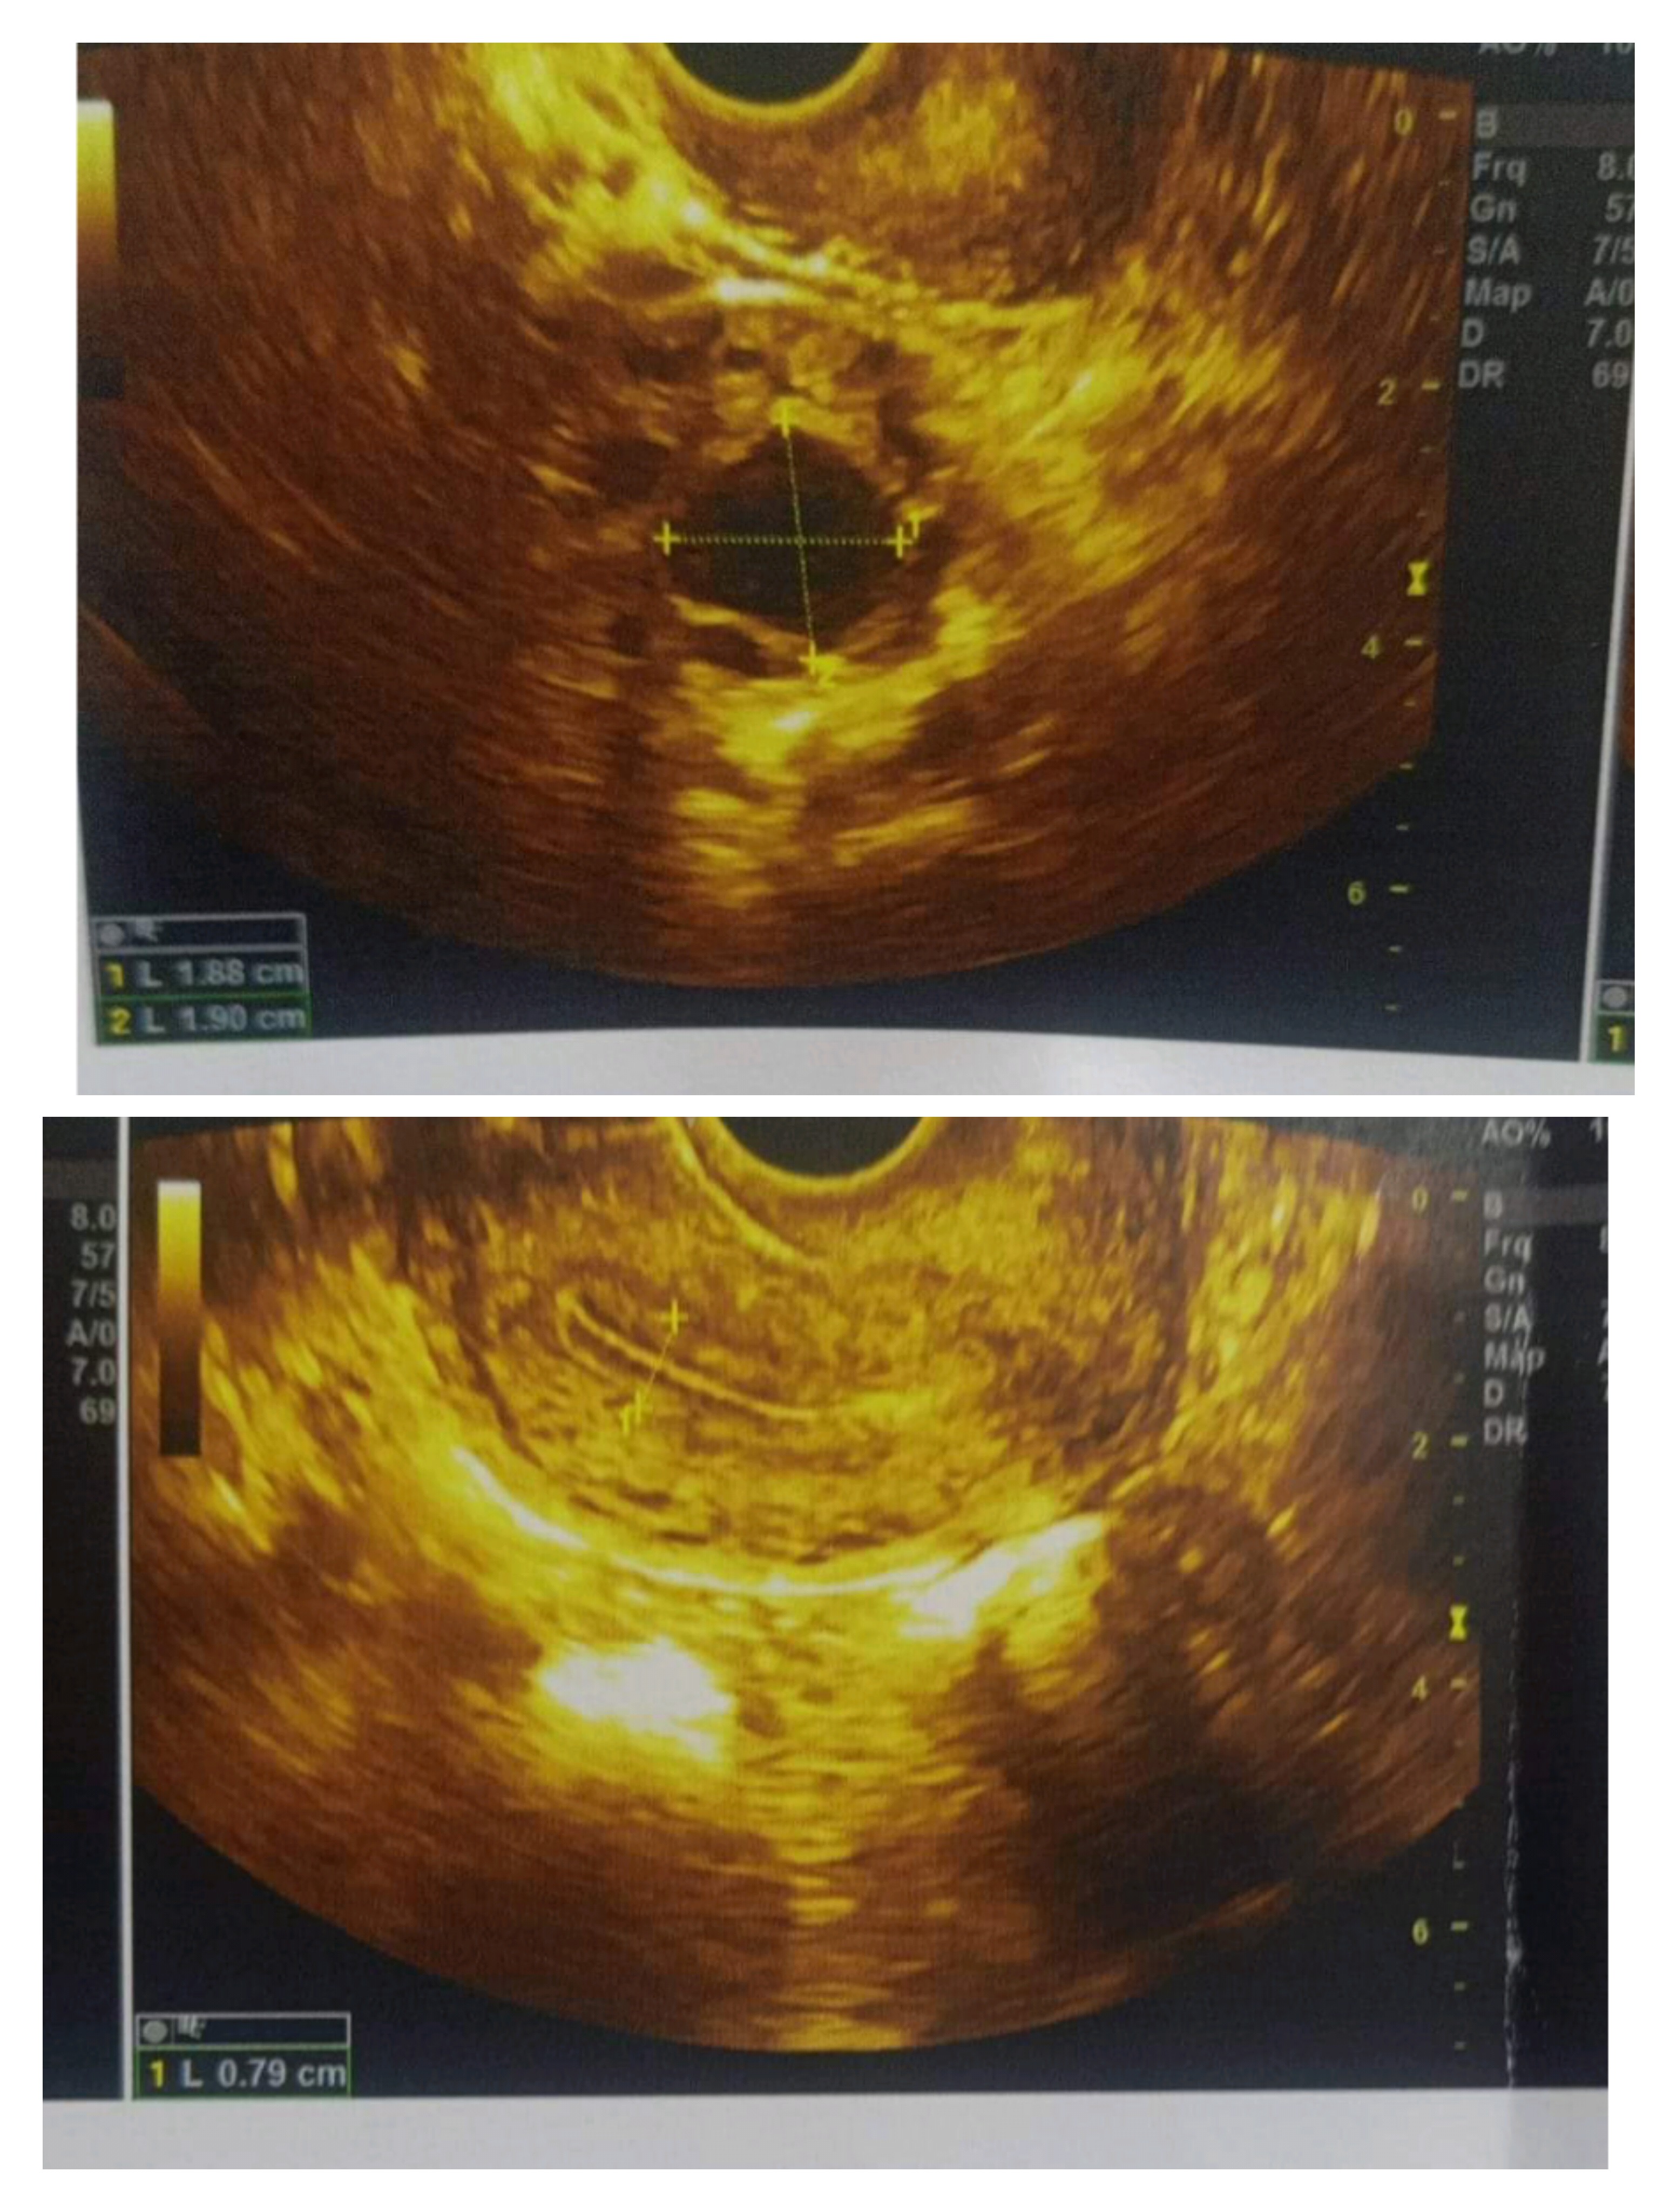

لو سمحتم دي صورة البويضه في اليوم العاشر من الدورة هل هي مناسبه لحدوث الحمل ولا حجمها صغير

بعد اذنكم دي ورقه السونار في اليوم 12 من الدوره الشهريه ممكن اعرف حجم البويضه كام و هل ممكن يحصل...